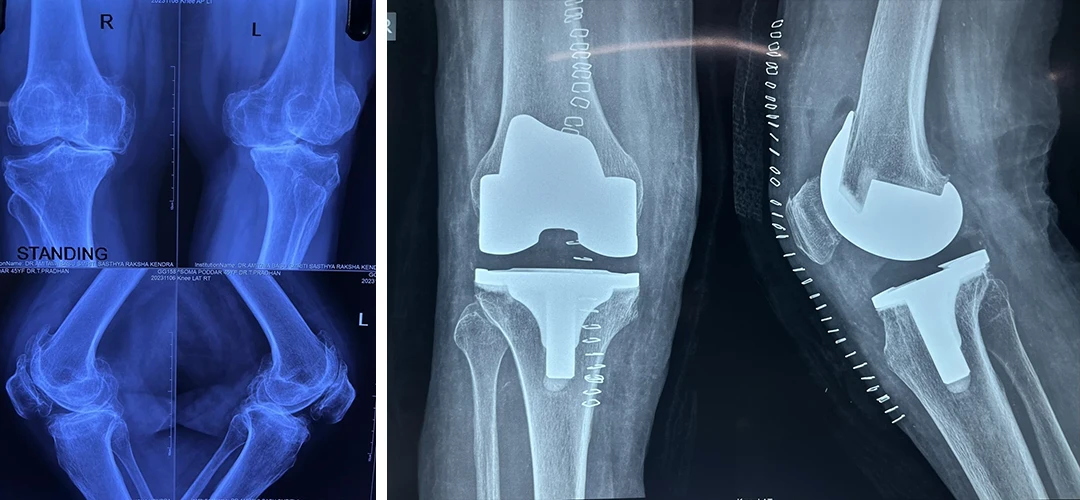

Total Knee Replacement

Are you having pain in your knees? Look no further, because Dr. Sanyal is the best choice for you. He specialises in total knee replacement surgery, offering you a solution to regain your mobility and live pain-free.